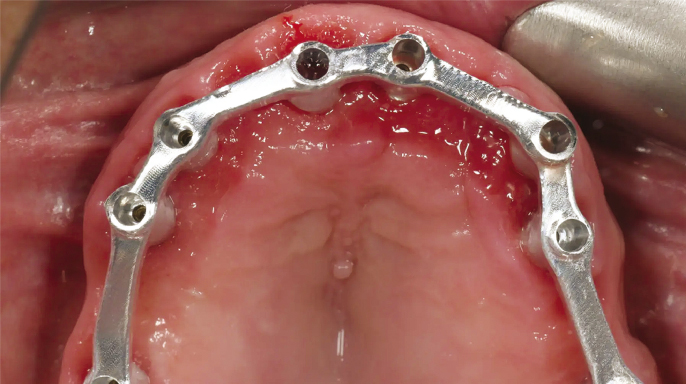

Moderní stomatologie prochází technologickou revolucí, kterou pohání integrace pokročilých digitálních nástrojů v diagnostice, plánování a léčbě. Mezi nimi se počítačem řízená implantologie stala základním pilířem, zejména u složitých výkonů, jako jsou estetické rekonstrukce a celková rehabilitace čelistního oblouku.

Digitální pracovní postupy ve stomatologii přinesly revoluci v přístupu odborníků ke složitým zákrokům – zlepšují přesnost, efektivitu a dosažené klinické výsledky. Mezi digitálními inovacemi se výrazně prosazují systémy pro plnou navigaci...

Použití pasivní a aktivní navigace při implantaci umožňuje dosáhnout relativně přesné pozice, hloubky i angulace štoly pro implantát, a tím pádem dobrou prediktabilitu protetického ošetření. Zejména používání operačních šablon pro pasivní navigaci…